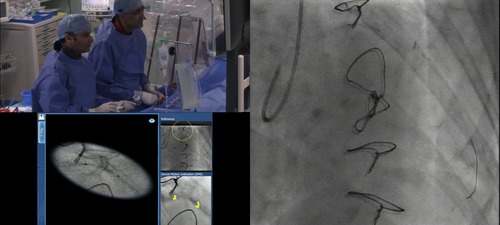

Prior to PCI the lesion underwent ballooning.  SyncVision was used to show the balloon inflation using automated image enhancement and stabilisation software.

• SyncVision to Co-register IVUS and angiographic images

• SyncVision automated Stent Enchancement